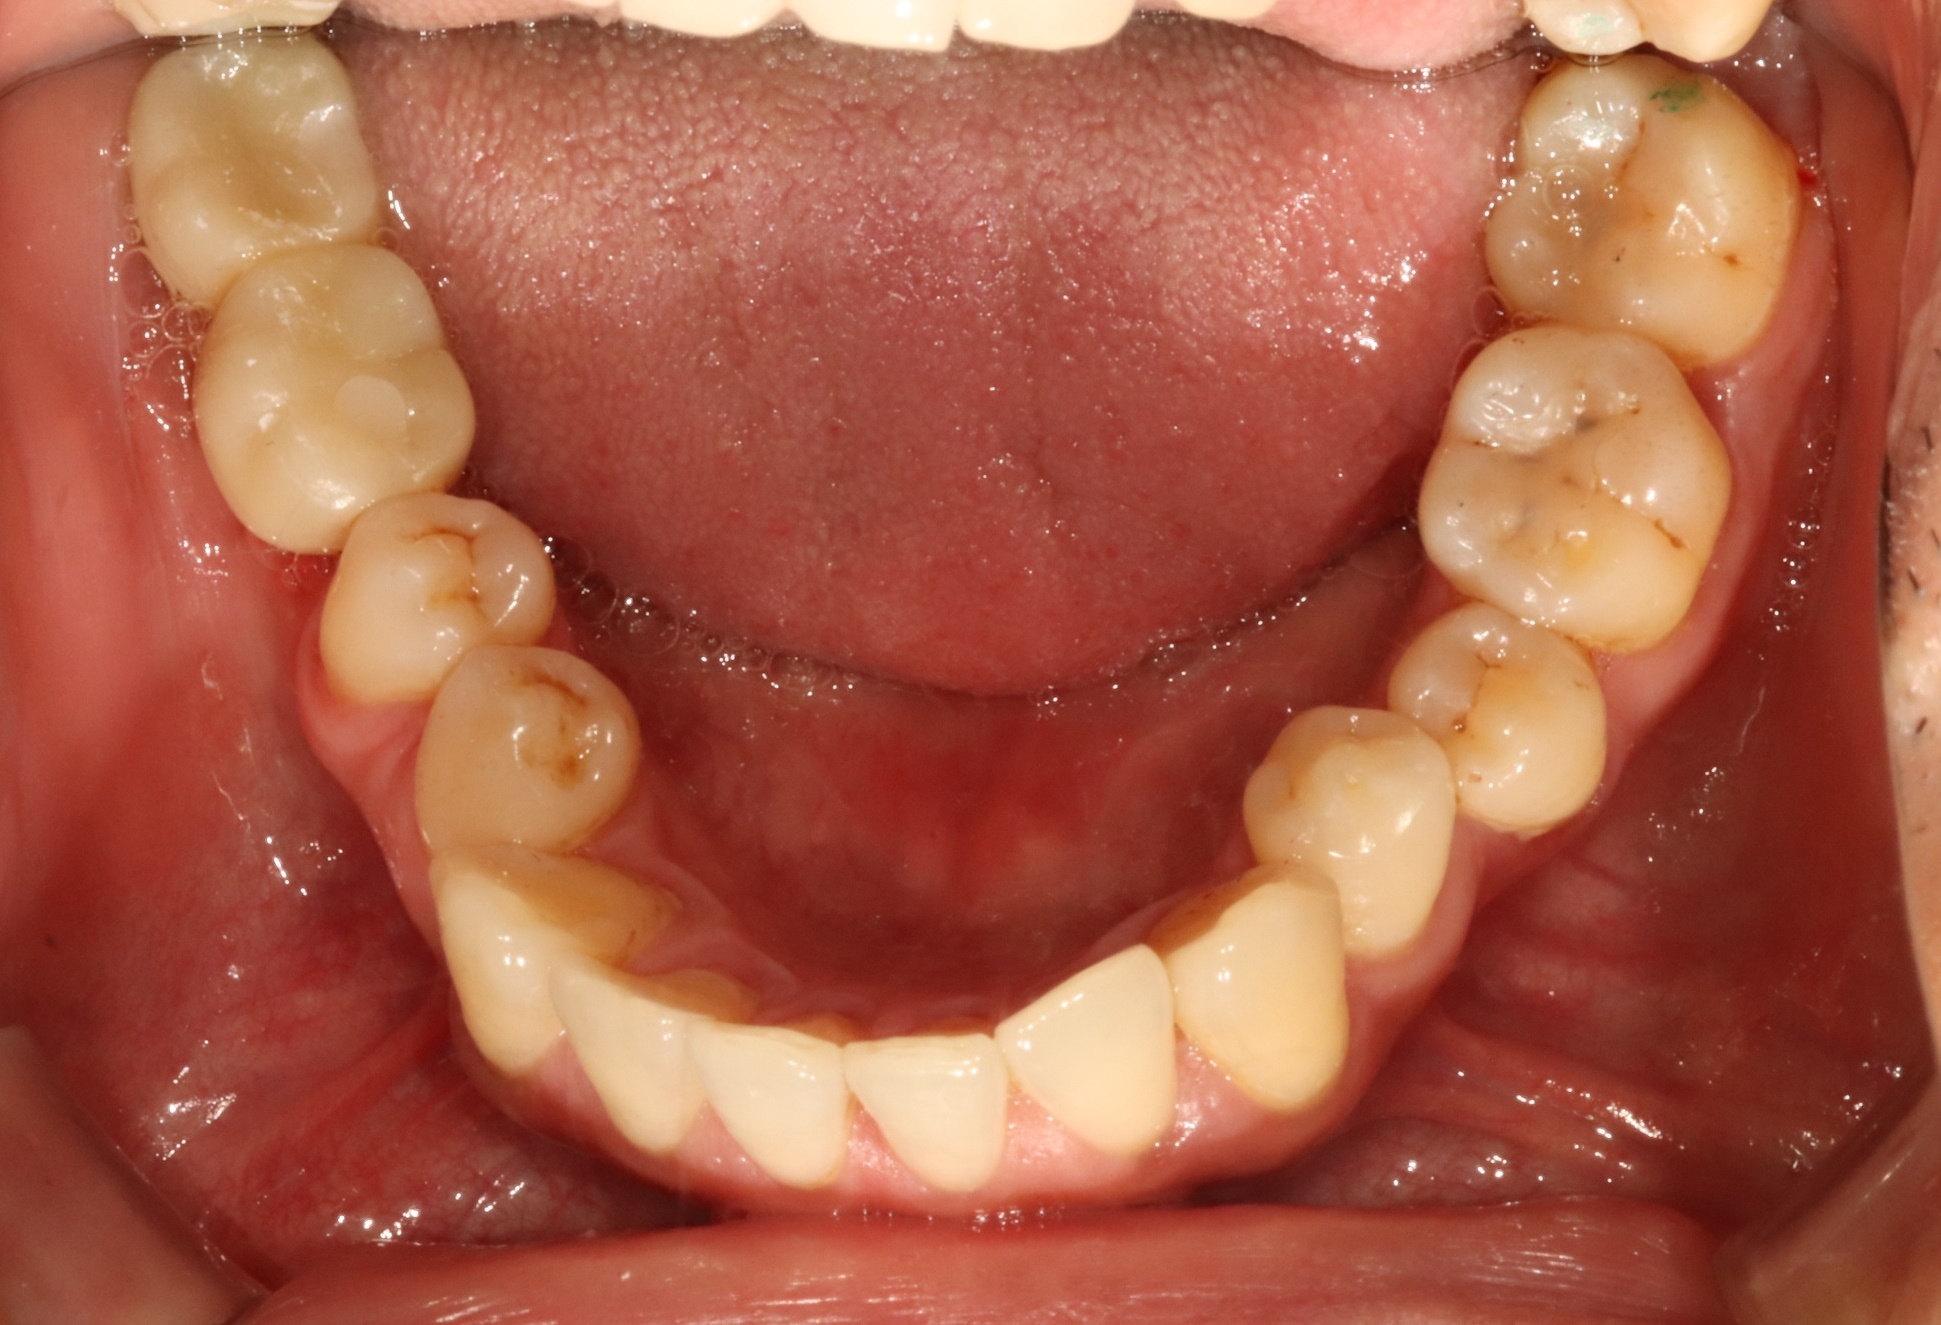

어금니 크라운

Before

After

대량 충치로 손상된 어금니 완전 복원